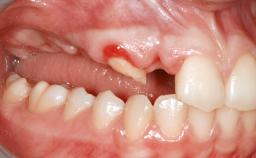

A 47-year-old woman who had suffered from aggressive periodontitis requiring a number of periodontal interventions over more than 10 years was referred by her general dental practitioner and periodontologist for bone augmentation and implant therapy. Her failing dentition had already been scheduled for extraction. The patient expressed a desire for implant-supported fixed restorations and esthetic improvement of her lower face. She had agreed to consult with a maxillofacial surgeon after the referring dentist had suggested bone augmentation. An initial examination by the maxillofacial surgeon revealed mobility of all residual teeth in a patient who was very unhappy with the function of her removable partial dentures. Due to periodontally migrated flaring teeth and loss of occlusal support, the vertical dimension of occlusion was dramatically reduced. The patient was displeased with her lower face because of deepened nasolabial, commissural, and supramental folds.

Periodontal Status History of periodontitis or genetic predisposition